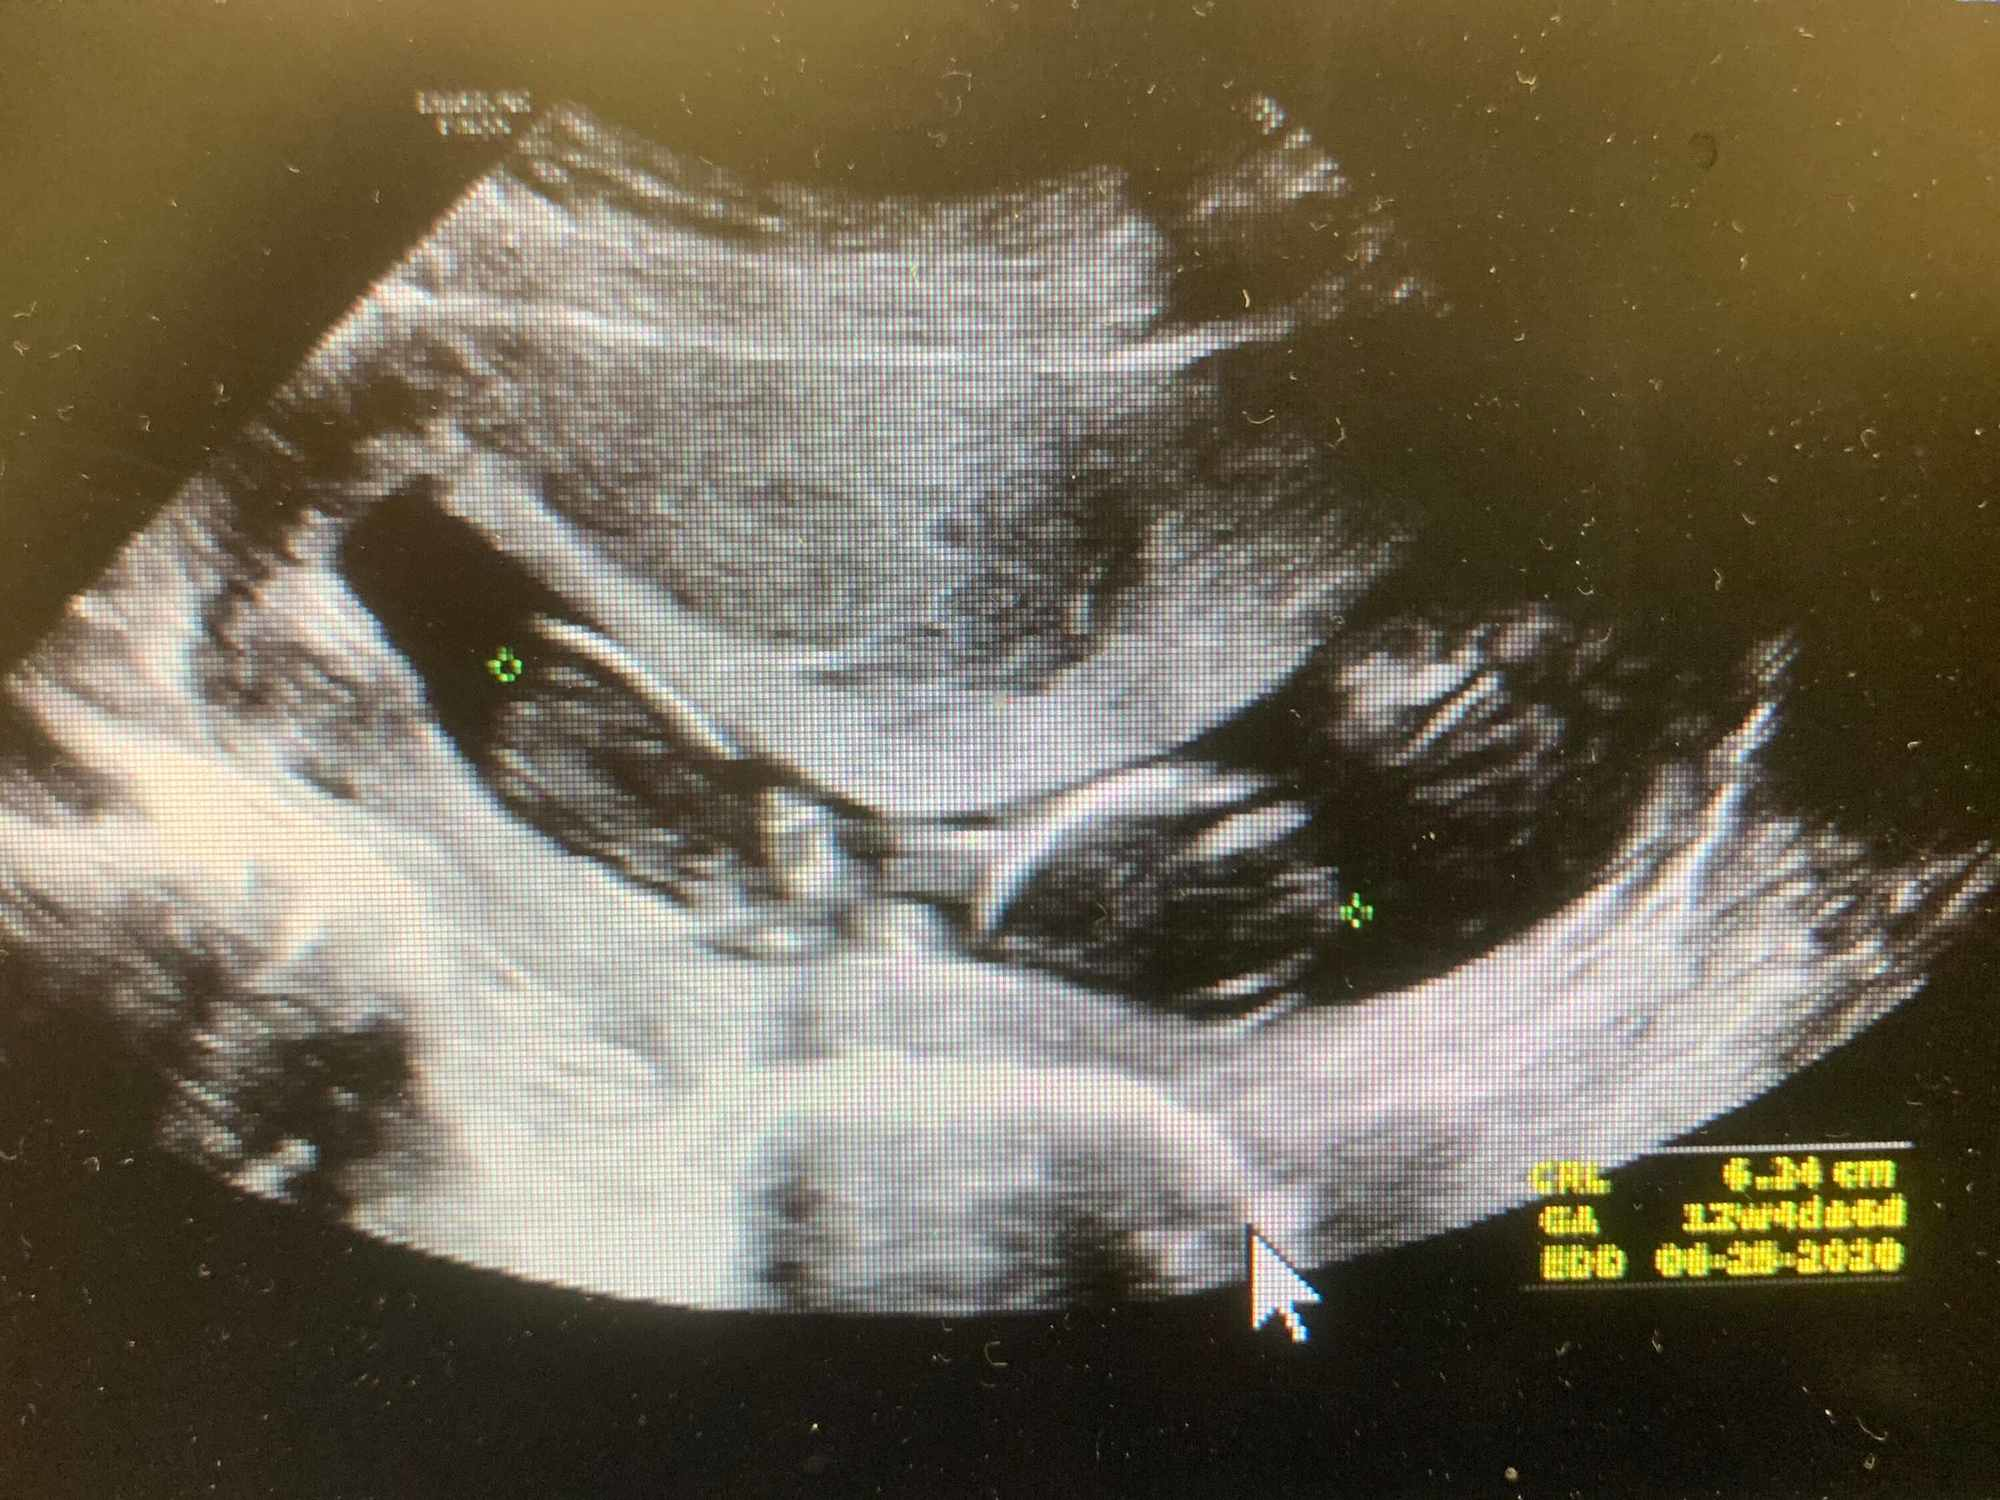

What Happens During the Scan ? When you have an ultrasound before an abortion it will be performed as an internal scan . In order to get clear pictures of your insides and the pregnancy at this early stage, we will need to use a trans-vaginal ultrasound probe . When you have an internal ultrasound at an abortion clinic:

With an ultrasound scan , they will tell you how far along you and if you have a viable pregnancy . Our medical services are free of charge . Have an ultrasound before taking the abortion pill or having a surgical procedure in order to know for sure (1) if you are pregnant; (2) how far along you are; (3) if you're experiencing an ectopic pregnancy .

The abortion pill can only be taken during the first 10 weeks of pregnancy, so it's important to know exactly how far along you are . An ultrasound scan is the most effective method of determining the potential due date and stage of pregnancy, even for women who carefully track their cycles and know when they've had unprotected sex .

Here are five key reasons to schedule an appointment for an ultrasound scan before your abortion : 1 . Your ultrasound results will help determine which abortion option you're eligible for . There are various methods of abortion available and your eligibility for each will most likely be determined by the stage of pregnancy you're in .

While a dating ultrasound should be encouraged, its absence is not an obstacle to scheduling an abortion for women who report that they know the date of their last menstrual period and/or of the at-risk sexual relations and for whom a clinical examination by a healthcare professional is possible (best practice agreement) .